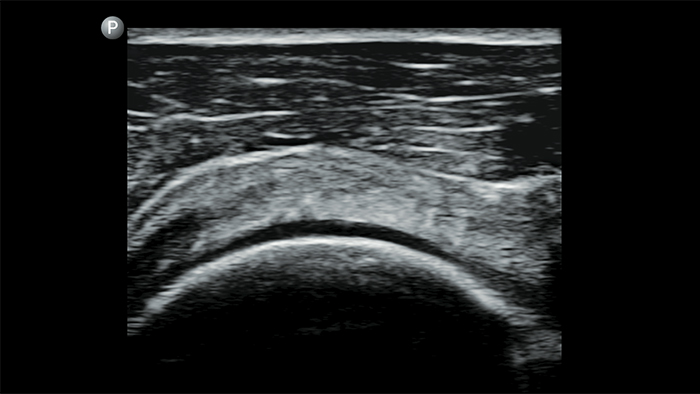

Start treatment with an accurate diagnosis

Lumify helps you see the fine details in muscles, joints, ligaments, tendons and cartilage to make a more accurate diagnosis of injuries.

Respond fast with whole-body imagery

Lumify can help you assess patients from head to toe, whether it’s plantar fasciitis, tendonitis or bursitis in the patellar tendon, or even shoulder instability in the rotator cuff.

Get the clarity of larger ultrasound systems with Lumify

SonoCT reinforces real tissue imaging while eliminating random artifacts. This technology produces images superior to conventional imaging in up to 94% of patients.